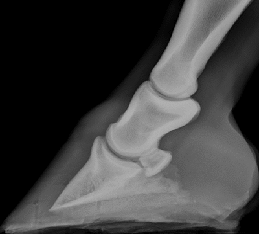

Equine Imaging

What's going on inside? Does your horse have a bone fracture? Is there a hoof abscess? Trouble with their teeth? We have digital x-rays to help see inside. And while it is faster and easier to do the x-rays in our clinics, we can bring the equipment to you if necessary.